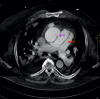

We present a case of a 56-year-old patient with obstructive sleep apnoea (OSA) presenting with acute decompensated heart failure and signs of cardiogenic shock. Echocardiography and CT imaging led to the diagnosis of acute type A aortic dissection (AD) complicated by aortopulmonary fistula (APF). The patient underwent successful surgical repair with complicated postoperative course including pulseless electrical activity arrest. This case highlights the underappreciated role of untreated OSA as a risk factor for AD. Furthermore, it presents an opportunity to review APFs as a rare complication of AD. We discuss the available evidence linking OSA and AD, review currently reported cases of APF, briefly outline the haemodynamics of this acute left-to-right shunt and discuss management of this rare but deadly complication.